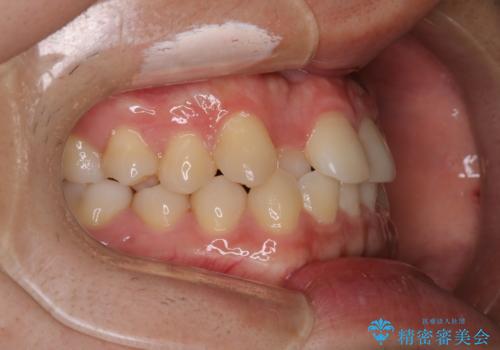

- 前歯のがたつきを主訴に来院されました。初診時、右上2番の口蓋側転位と右下7番の舌側傾斜が認められました。

インビザラインにてIPRと歯列弓拡大を行い、ゴム掛けで噛み合わせを改善する治療計画を立てました。

治療期間1年で、主訴である前歯のがたつきを改善出来、

奥歯の噛み合わせも良くなりました。